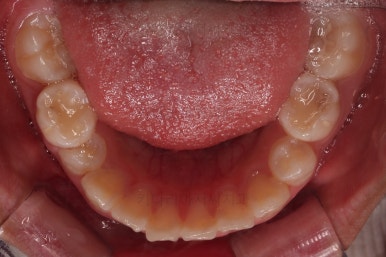

부산소아교정 초진 시 입안의 모습입니다.

윗니가 아랫니보다 많이 앞에 나와있고요.

심지어는 틈새가 벌어지기까지 했습니다.

윗니가 배열 되어있는 U자 형태(그릇 형태)가 아랫니보다 좁은 양상이고요.

이런 앵글씨 2급 부정교합에서는 아랫니가 윗니와 만나기 위해 솟구쳐서 과개교합(아래 앞니가 윗니 뒤쪽으로 깊숙히 올라가 있는 상태)이 나타나기까지 합니다.